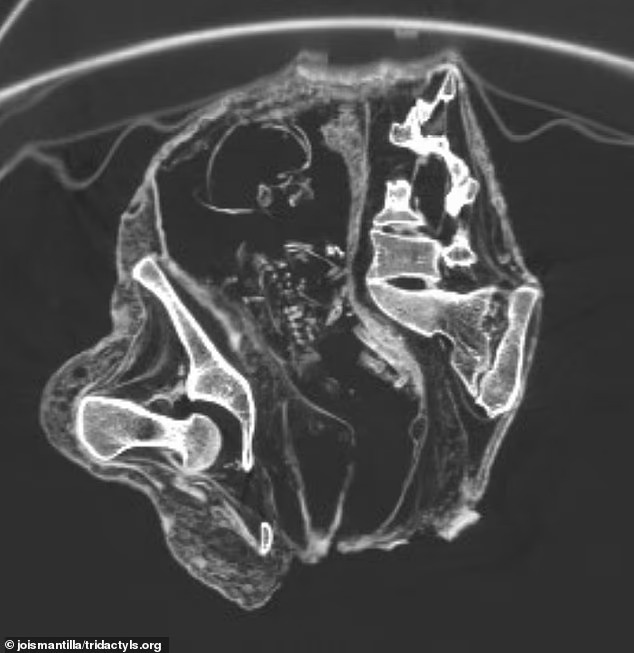

Компьютерная томография зафиксировала «плод», лежащий на спине, с головой внизу возле области живота и груди, а руки ближе к тазовой области.

Учёные предположили, что его кости были ещё мягкими, только начинали твердеть, когда Монсеррат умерла, из-за чего части позвоночника и рёбер не смогли срастись. Они определили возраст «плода» по длине его бедренной кости — 43 миллиметра, что используется для оценки гестационного возраста при пренатальном УЗИ, что указывает на срок менее 30 недель.

Сканирование показало, что плод со временем высох в утробе, сказал он. По мере усыхания тканей мышцы матки сохранили общую форму, но мягкие, неразвитые кости черепа и лица сместились.

Когда учёные цифрово реконструировали плод, они обнаружили, что его лицо оказалось повёрнутым назад.

Учёные заявили, что это объясняет, почему позвоночник и рёбра выглядят сломанными или смещёнными на снимках.

Некоторые части костей, особенно ростковые зоны на концах, вообще не видны на КТ-изображениях.